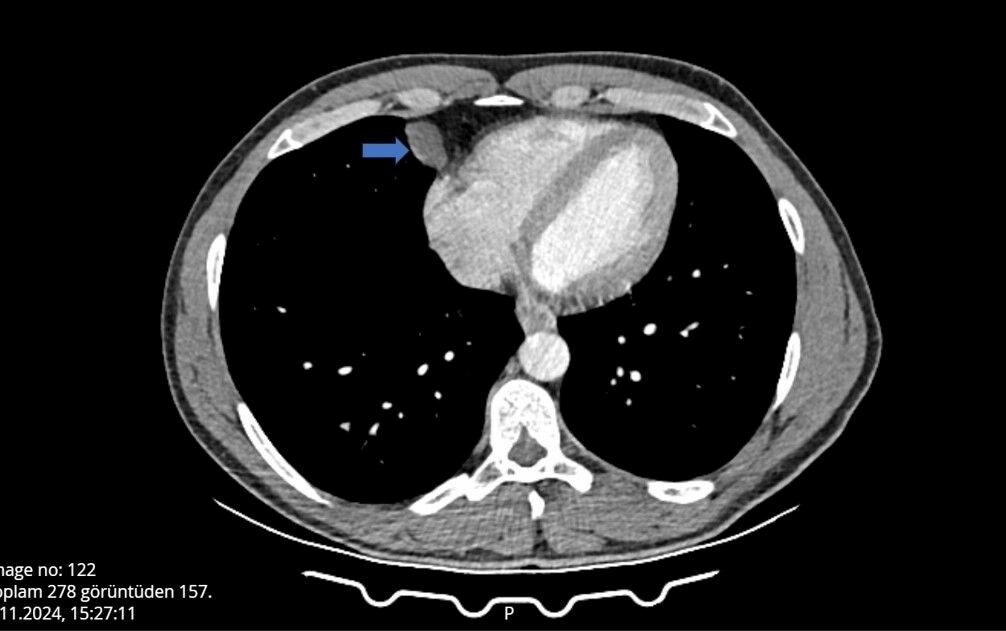

Can, nefes almakta güçlük yaşayınca Şanlıurfa’nın Akçakale ilçesinde hastane aciline başvurdu. Burada tomografisi çekilen Can’ın, akciğer ile kalbinin arasında bir kist olabileceği belirtildi.

Gerekli tetkikleri yapılan Ömer Can’ın, belirtilen bölgesinde yaklaşık 2 santimlik bir kist olduğu tespit edildi ve hemen ameliyata alındı. Göğüs Cerrahi bölümünde Video Yardımlı Torakoskopik Cerrahi (VATS) yöntemiyle gerçekleşen ameliyat yaklaşık 10 dakika sürdü.